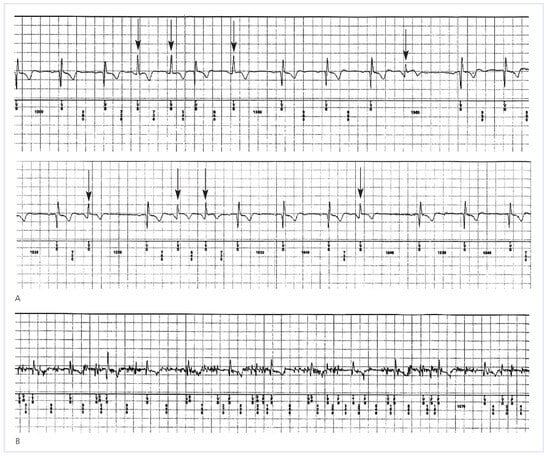

Figure 3.

Inappropriate detection of AF. Shown in (A) an example of inappropriate detection of AF triggered by irregularities of R-R intervals due to frequent ventricular premature beats (arrows). (B) shows another example of inappropriate detection of AF due to high-frequency muscle noise detection. The patient was exercising at that time wearing a backpack.